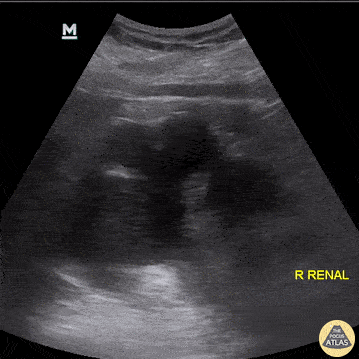

POCUS evidence of severe right renal hydronephrosis, as identified in a patient who had an ipsilateral 2.5cm mid-ureteral calculus. Aaron Inouye, PA-C, North Canyon Medical Center @PAintheED